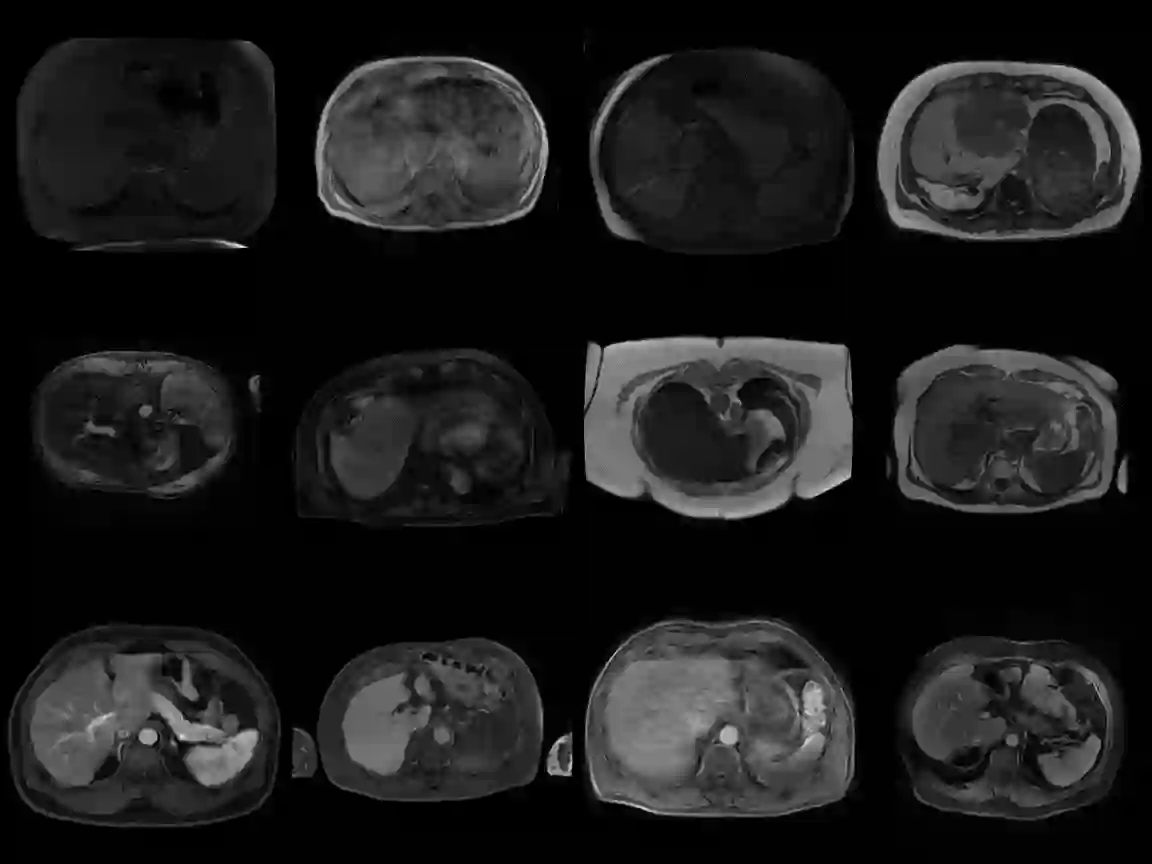

Clinically deployed segmentation models are known to fail on data outside of their training distribution. As these models perform well on most cases, it is imperative to detect out-of-distribution (OOD) images at inference to protect against automation bias. This work applies the Mahalanobis distance post hoc to the bottleneck features of a Swin UNETR model that segments the liver on T1-weighted magnetic resonance imaging. By reducing the dimensions of the bottleneck features with principal component analysis, OOD images were detected with high performance and minimal computational load.